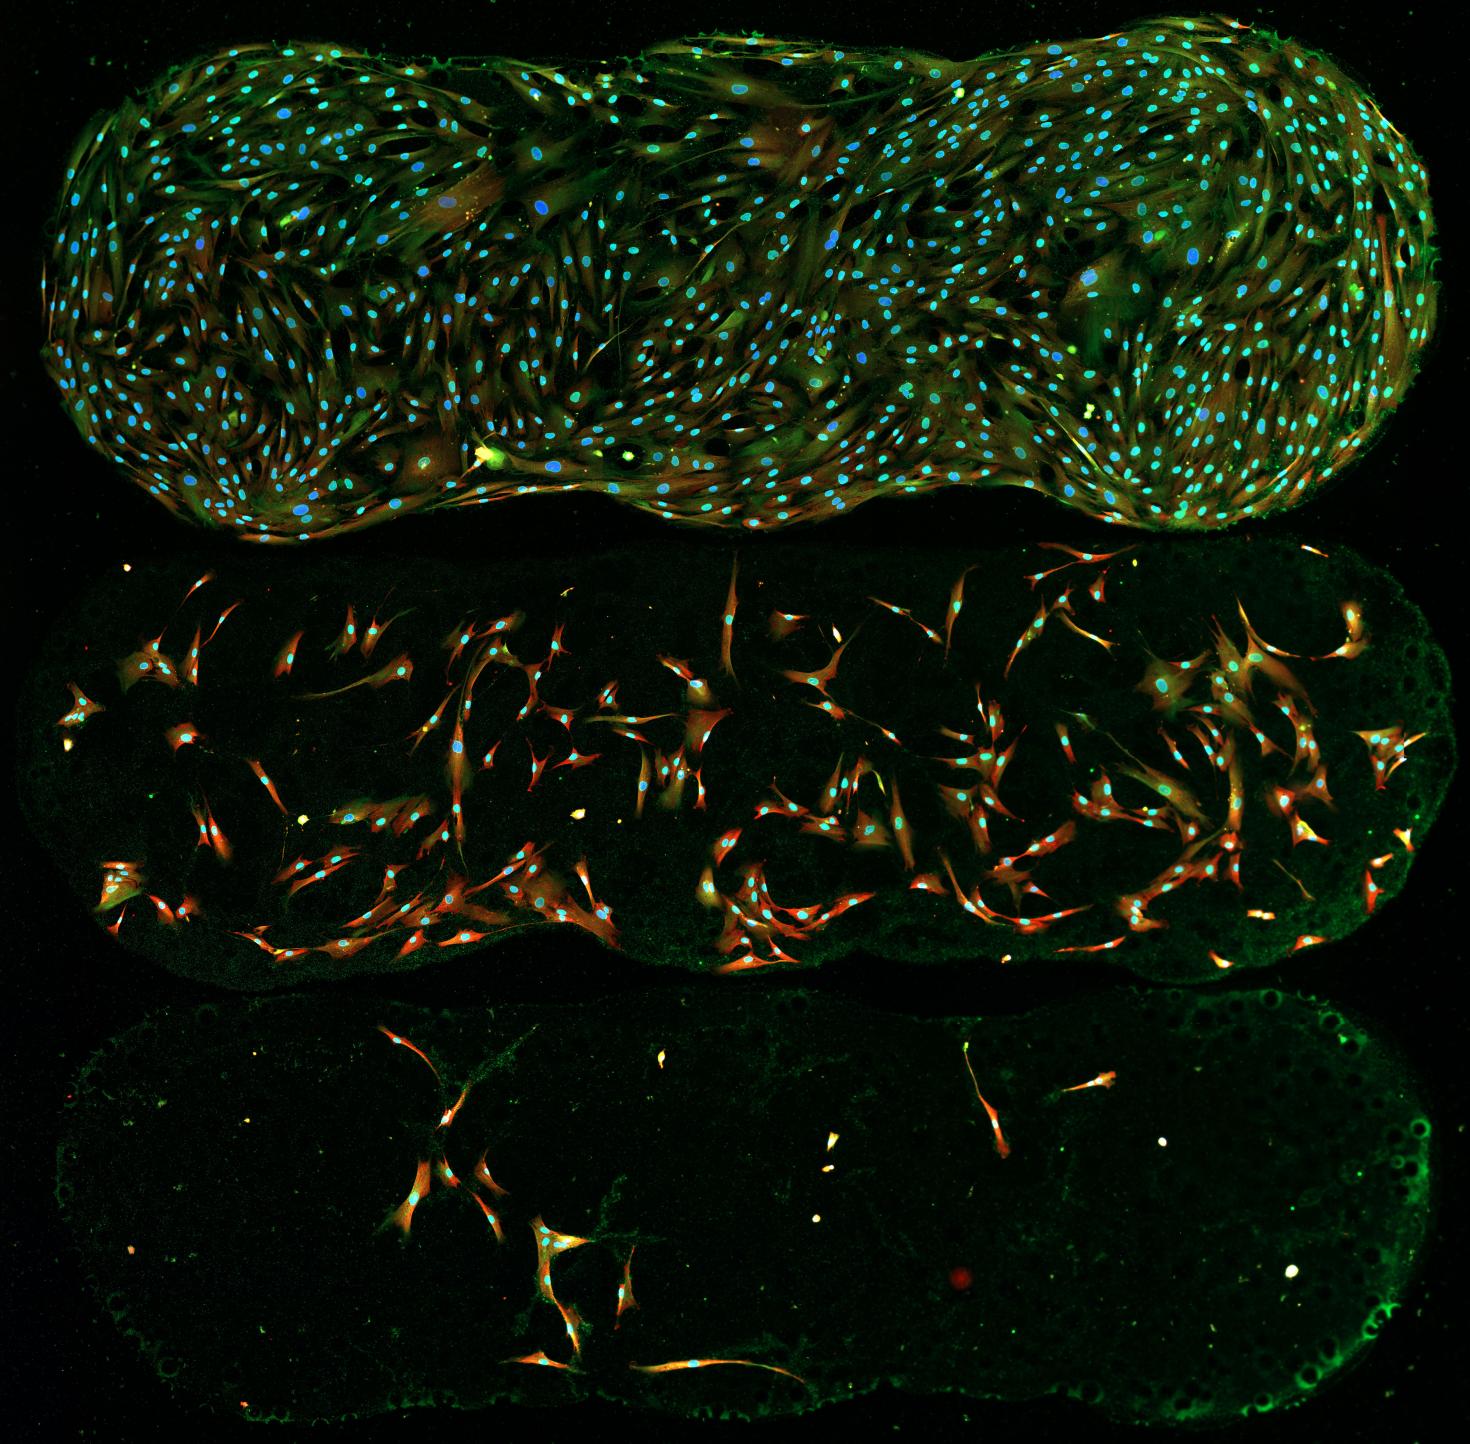

The image depicts human macrophages infected with Yersinia pestis Kim 5 (plague) 10:1 after 24 hours. Here DNA is blue, Y. pestis is green and bacterial death is marked in red. Prepared and visualized by Katie Van Etten (UIUC Anthropology, 2017) as part of the Brinkworth Evolutionary Immunology and Genomic lab's research into the evolution of human immune function. Funded by NSF grant BCS-1750675.

Image preparation and photo credit: Katie Van Etten

Others involved in the production of this image: Keaton McClure (MCB, 2019), Priya Bhatt (Anthropology, 2021), Will Widick (Vet Med, 2019), Alex Alvarado (Anthropology, 2021), Jessica F. Brinkworth (Anthropology, PI), Luis Barreiro (University of Chicago, Co-PI)

Instrument: Zeiss LSM 700 four laser scanning confocal microscope, at Carl R. Woese Institute for Genomic Biology